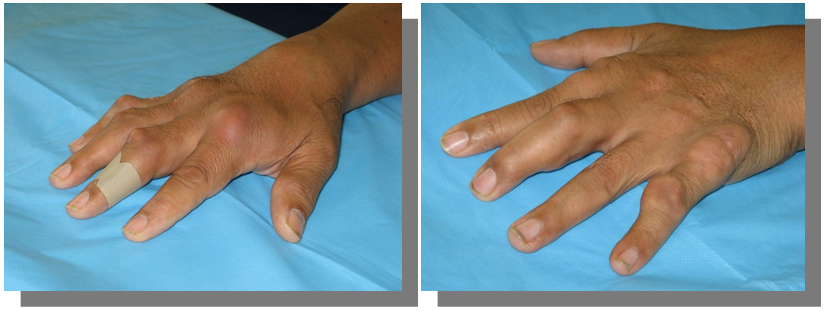

Hands (Figure 1)

Figure 1 Inflamed dorsum of the right hand, skin redness, swelling, and tenderness. Multiple swellings on left hand.